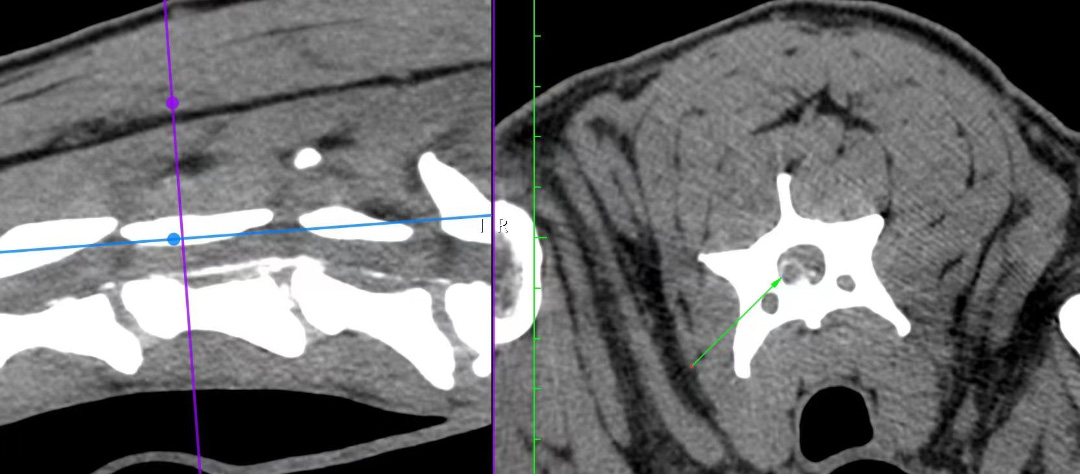

CT检测结果显示C4-C5汉森I型椎间盘脱出压迫神经